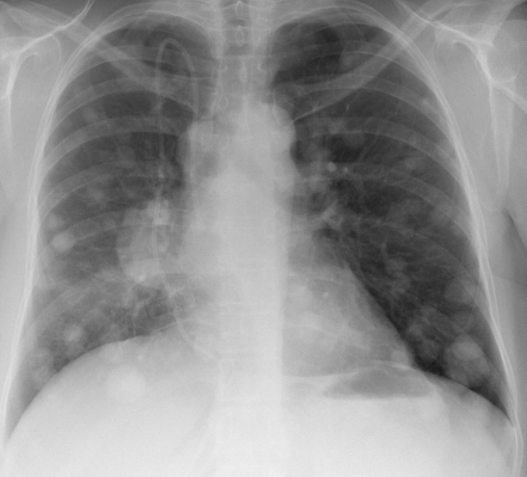

Lacher de Ballon

Cannonball en anglais

Distribution vasculaire = Prédominent aux plages inf.